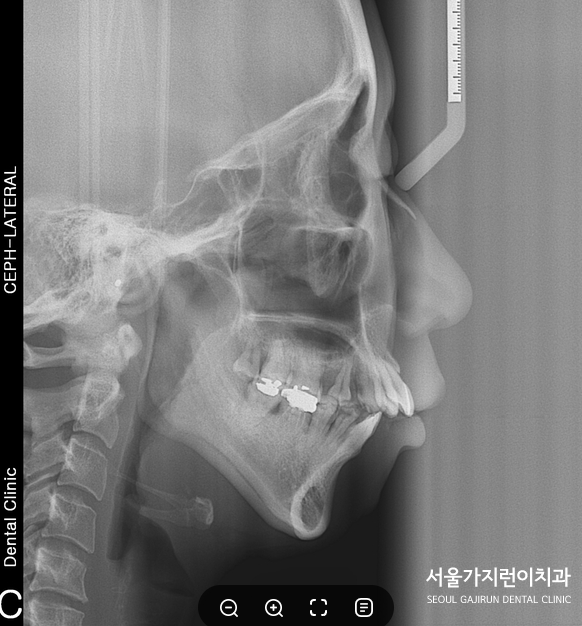

그래서 환자분의 경우 확실한 염증조절치료 후 교정을 진행했는데요. 하악 과두가 상당히 흡수가 된 상태여서 턱관절이 약해져 있는 상태였습니다. 그래서 치료 도중에 정출이 일어나지 않도록 치료하는 것이 중요했는데요. 상기 환자처럼 전형적인 계란형 얼굴로 아래턱이 작고 무턱 증상이 있는 경우라면 얼굴이 길어지고 입술이 벌어지는 증상이 생겨날 수 있어서 주의하면서 교정치료 플랜을 수립해야 했어요. 그래서 환자분의 경우에는 설측교정으로 진행을 도와드렸는데요.

설측교정으로 할 경우 협착교정에 비해 제2대구치의 설측교두의 수직적 정출 가능성이 줄어들어 결과적으로 하악의 시계방향 회전 가능성이 현저히 줄어들게 됩니다. 따라서 환자분의 경우 나머지 세 곳의 소구치를 발치하고 미니스크류에 교정용 고무줄을 잡고 돌출입교정을 진행했는데요. 상악 전치를 후방으로 이동시키면서 미니스크류의 힘으로 설측교두의 정출을 막는 정도가 아닌 함임시켜 하악골이 반시계 방향으로 회전할 수 있게 교정을 진행했습니다. 이렇게 하면 얼굴길이를 짧게 만들 수 있으면서 무턱 증상을 개선할 수 있기 때문입니다.